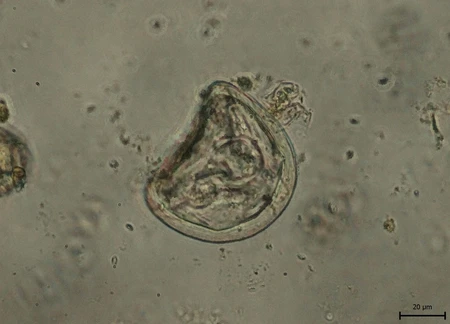

Les protozoaires et cestodes

Nommez les protozoaires et les cestodes illustrés.

Protozoaire

Cestode